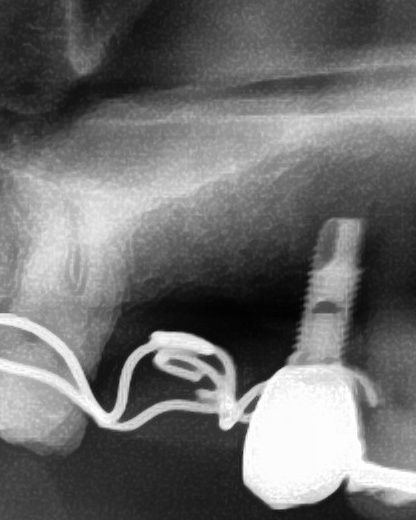

開けた穴に、専用道具を使ってネジを締めるように長さ2センチ程のインプラントを骨に埋め込んでいきます。

しっかりとインプラント埋め込まれた後は、動揺がないか、噛んだ時に当たらないかなどを確認して、最後にパノラマ写真を撮影して今回のオペは終了となりました。